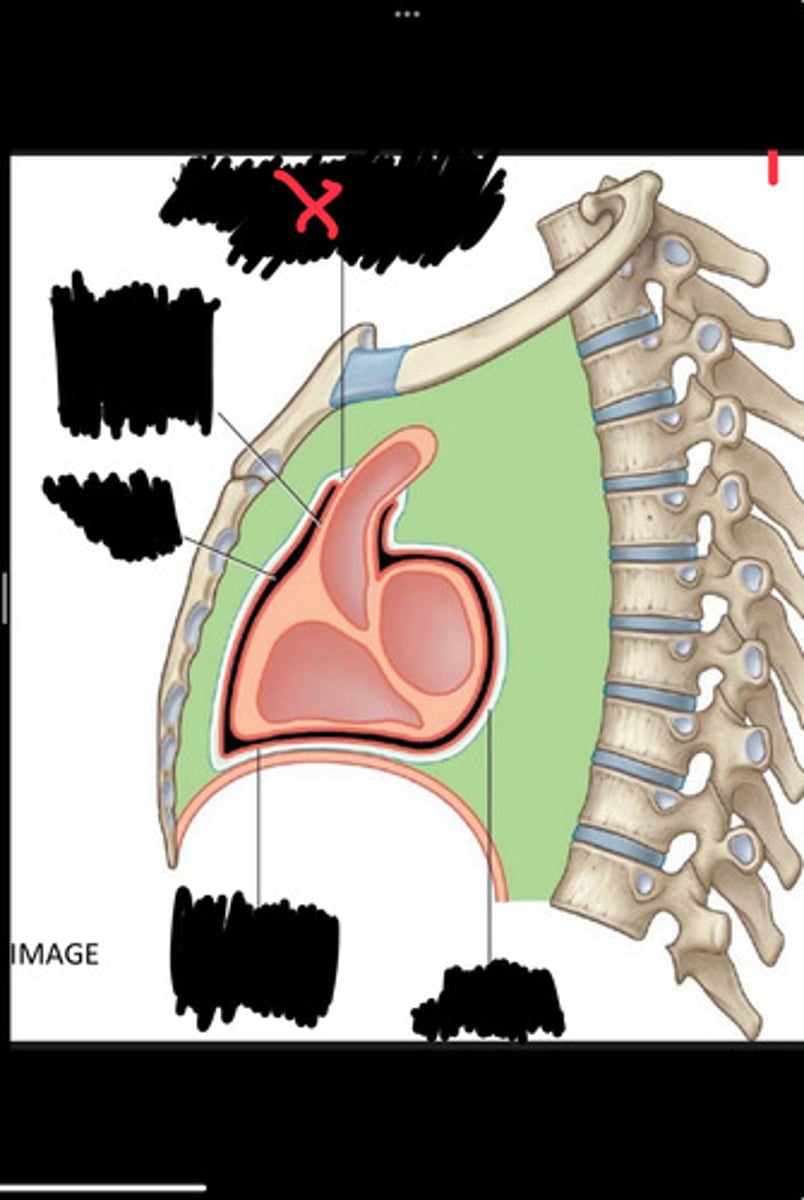

Fibrous pericardium

Parietal layer of serous pericardium

Pericardial cavity

Visceral layer of serous pericardium

Junction between fibrous pericardium and adventitia

Heart

Thoracic aorta

Rib 1